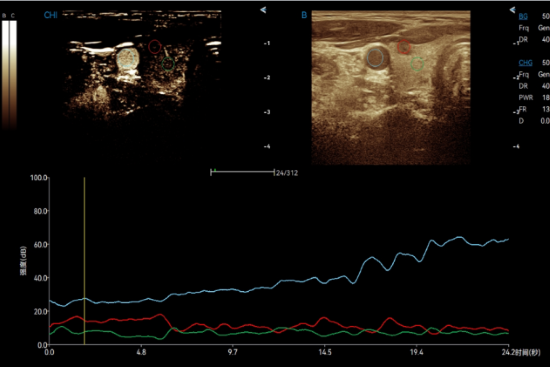

CHI QA visualizes the organ blood perfusion status with enhanced contrast. Dual mode comparison and time-intensity curves provide objective results for tumor diagnosis.